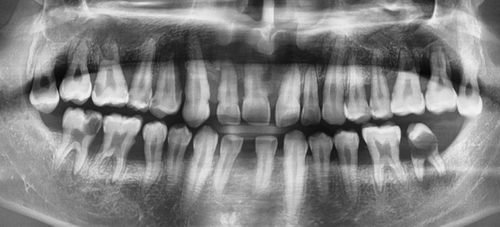

처음오셨을 때 상태이구요

아직 젊은 20대 분이신데도 X-ray상 어금니 쪽에 충치가 굉장히 많으셨고 잇몸뼈도 많이 녹아있는 상태였습니다.